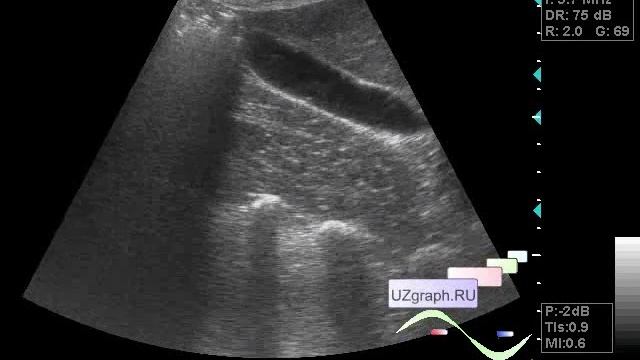

Нормальные размеры желчного пузыря: медицинские изображения